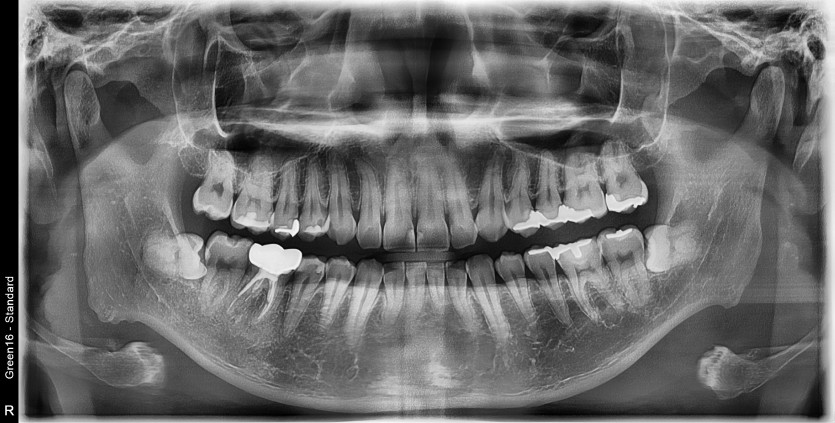

#38, 48 사랑니 발치

구강 외과 전문의가 당일 발치했습니다.